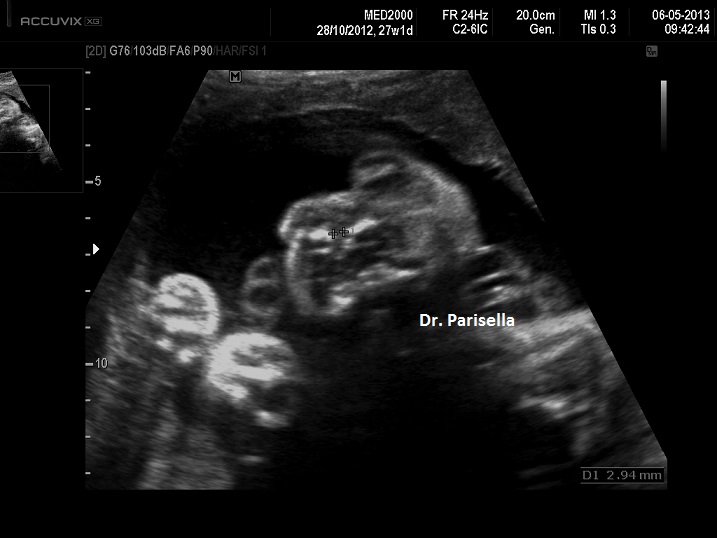

La Diagnosi Prenatale si basa su:

-         Anomalie Vertebrali: emivertebra cervicale, fusione vertebrale, scoliosi tratto cervicale.

-         Cardiopatie congenite: Tetralogia di Fallot, Ventricolo destro a doppia uscita, anomalie delle vene cave.

-         Anomalie del SNC: lipoma del corpo calloso, idrocefalia, malformazione di Chiari, encefalocele, ipoplasia del verme cerebellare, megacisterna magna, ipoplasia unilaterale del cervelletto.